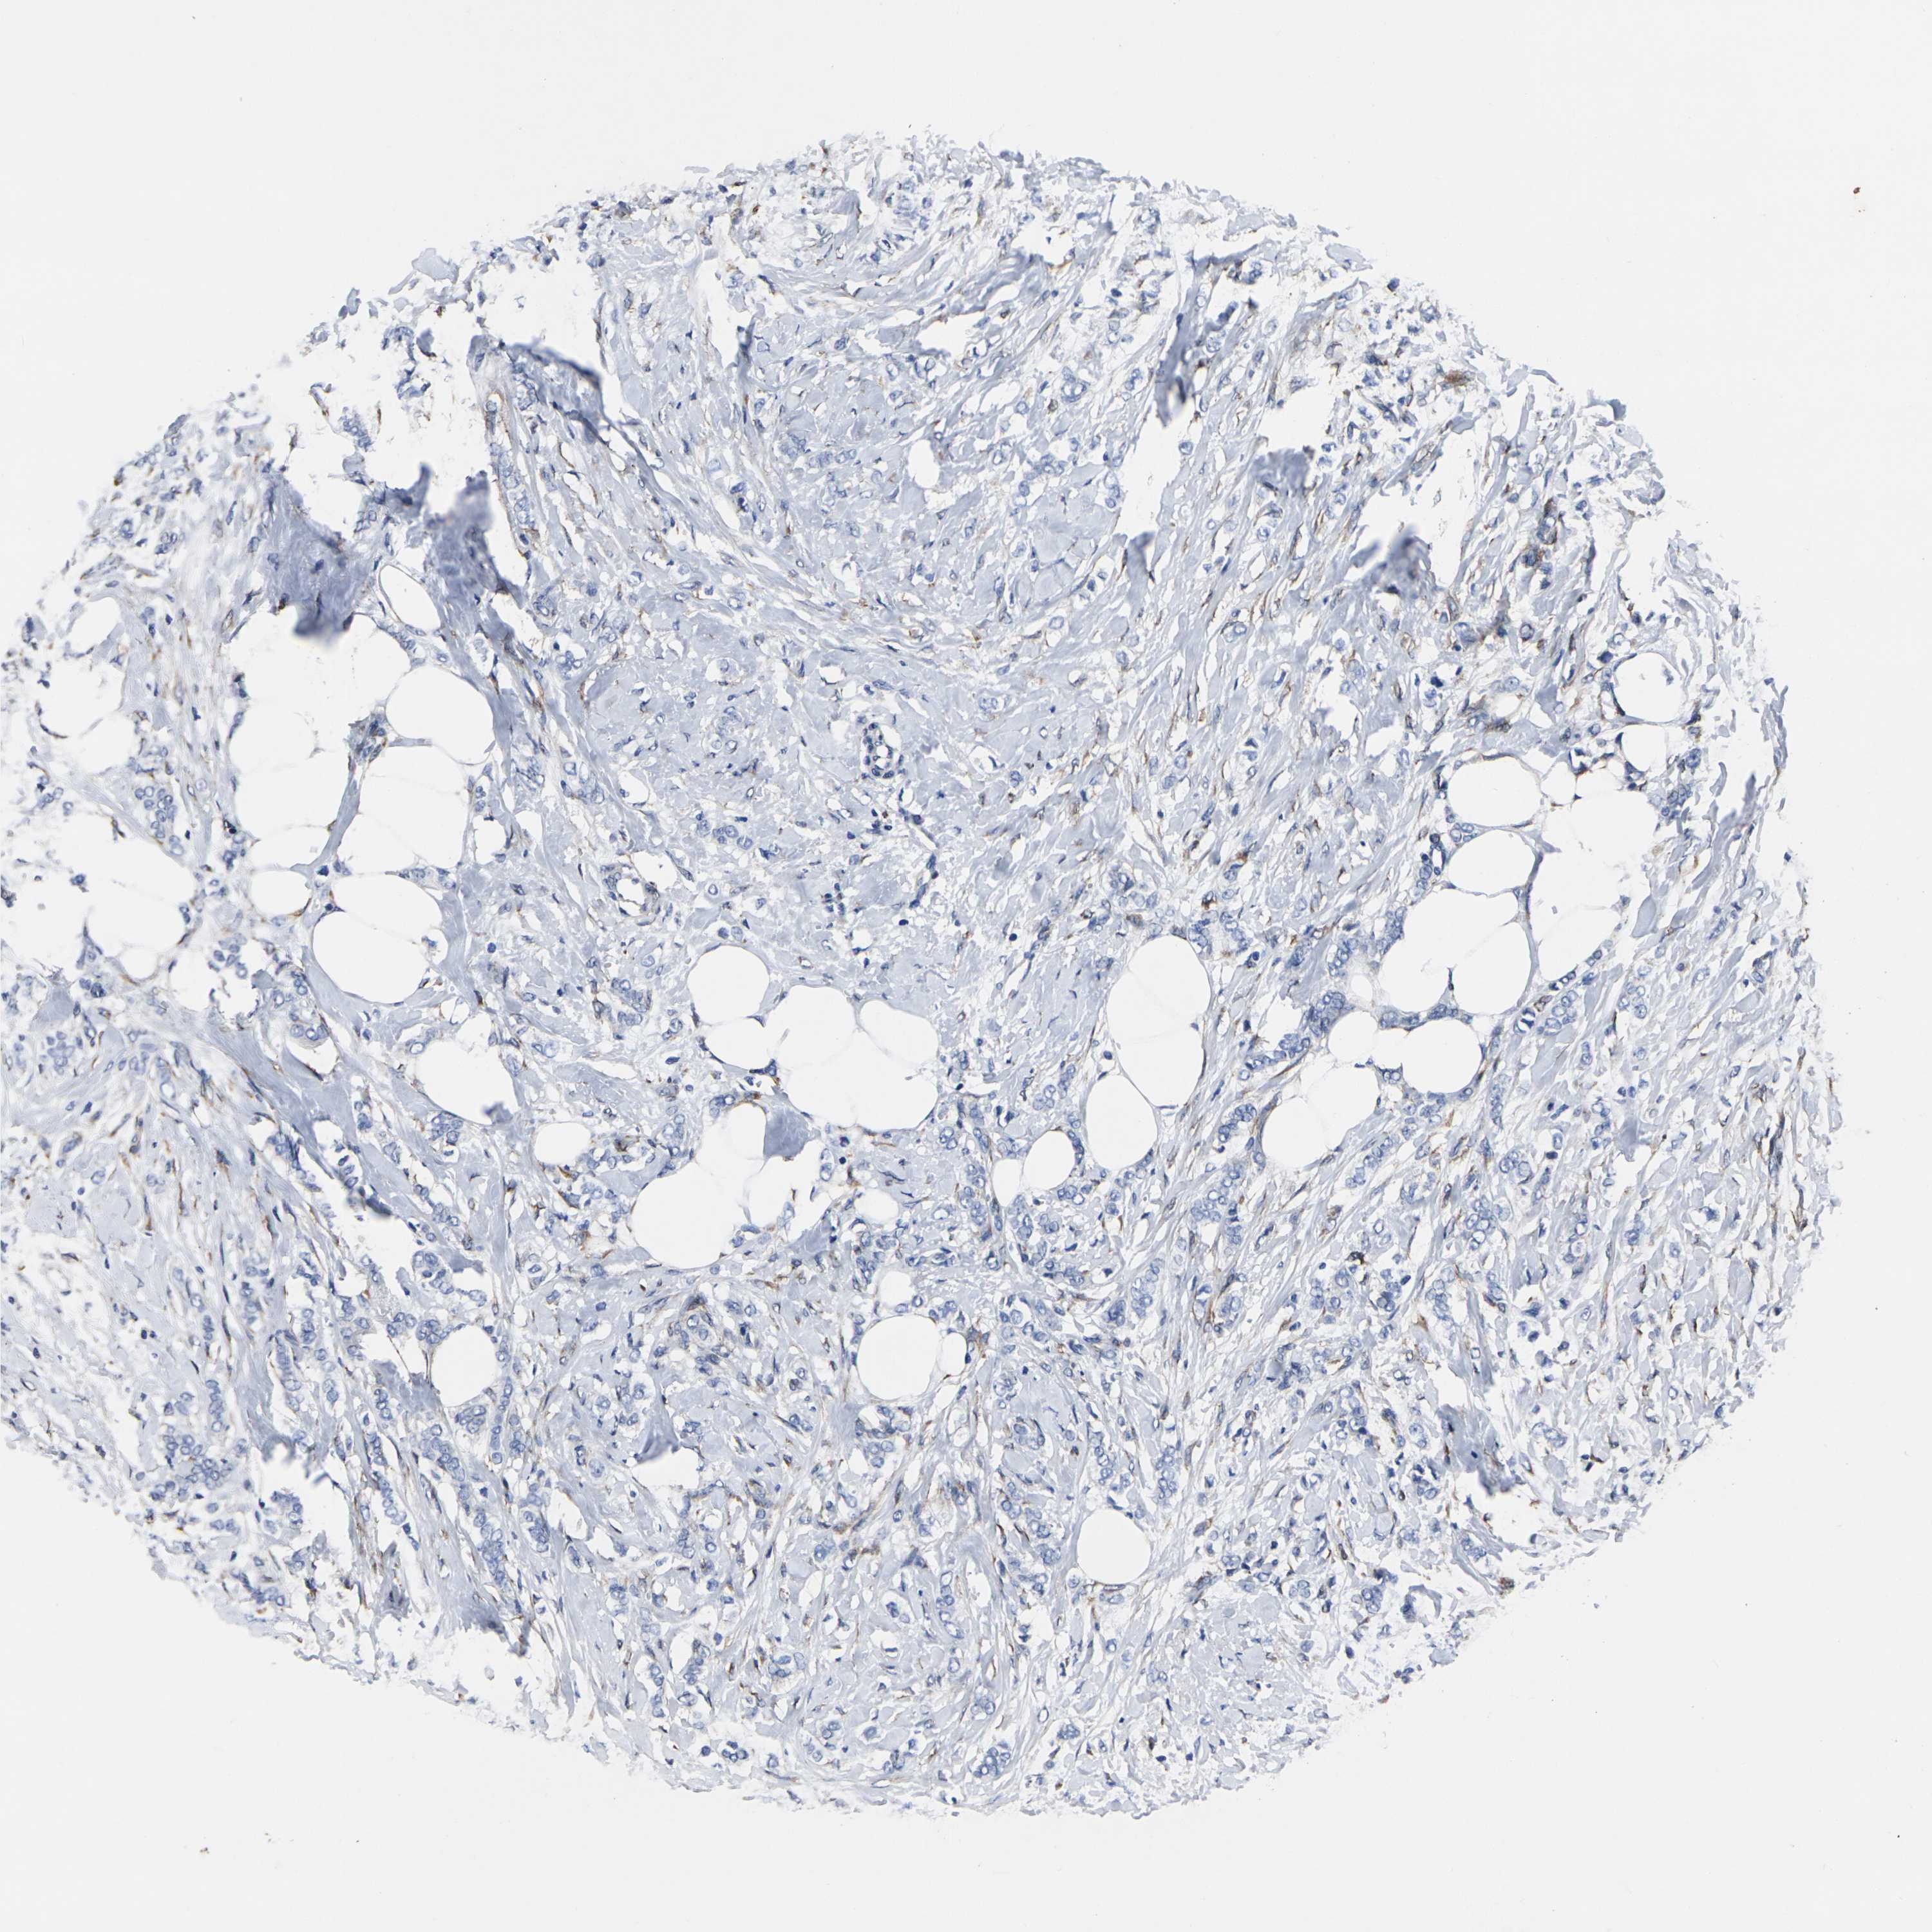

CANCER BREAST CANCER Show tissue menu

BRCA TCGA BRCA VALIDATION PROTEIN EXPRESSION

ANTIBODIES

AND

VALIDATION